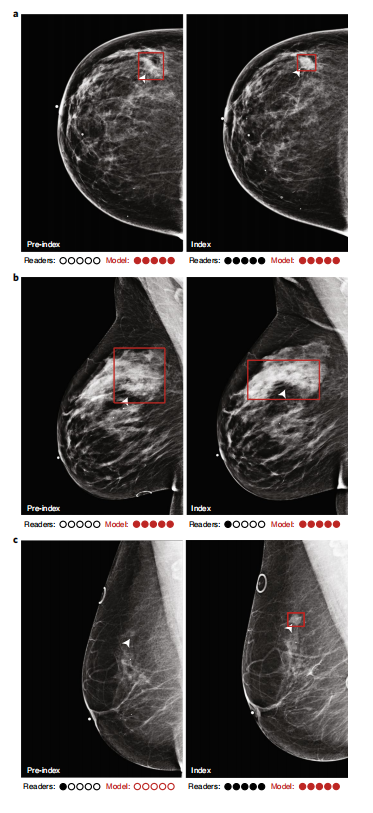

Fig. 3 | Examples of index and pre-index cancer exam pairs. Images from three patients with biopsy-proven malignancies are displayed. For each patient, an image from the index exam from which the cancer was discovered is shown on the right, and an image from the prior screening exam acquired 12–24 months earlier and interpreted as negative is shown on the left. From top to bottom, the number of days between the index and pre-index exams is 378, 629, and 414. The dots below each image indicate reader and model performance. Specifically, the number of infilled black dots represent how many of the five readers correctly classified the corresponding case, and the number of infilled red dots represent how many times the model would correctly classify the case if the model score threshold was individually set to match the specificity of each reader. The model is thus evaluated at five binary decision thresholds for comparison purposes, and we note that a different binary score threshold may be used in practice. Red boxes on the images indicate the model’s bounding box output. White arrows indicate the location of the malignant lesion. a, A cancer that was correctly classified by all readers and the deep learning model at all thresholds in the index case, but detected by only the model in the pre-index case. b, A cancer that was detected by the model in both the pre-index and index cases, but detected by only one reader in the index case and zero readers in the pre-index case. c, A cancer that was detected by the readers and the model in the index case, but detected by only one reader in the pre-index case. The absence of a red bounding box indicates that the model did not detect the cancer.

图3展示了通过对比索引检查与前一次筛查结果进行分析的病例实例。图中显示的是三位经活组织检查证实为恶性的患者的影像资料。对于每位患者而言,在右侧部分展示了发现癌症时所使用的索引检查影像,在左侧则呈现了12至24个月内进行过的一次阴性筛查结果影像。从上至下依次标明三种病例中索引检查与前一次筛查之间的天数分别为378天、629天和414天。在每张影像下方标注了不同评价指标的表现情况:黑色标记代表五位观察者中至少有一位成功识别出病变;红色标记则表明模型识别出病变的具体区域位置;白色箭头则指出了恶性病变在影像中的具体位置。研究重点放在模型在五个二元分类阈值下的表现评估上,并提出了几个关键观察结果:第一,在索引病例中所有观察者及深度学习系统均能准确识别所有病变样本;但在前一次筛查结果中仅模型发现了部分病变样本;第二,在两种情况下模型均识别到了所有病变样本;但仅在索引病例中有一位观察者能够检测到这些病变;第三,在索引病例中所有观察者及模型均能识别到特定病变样本;而在前一次筛查结果中标识出这些病变时仅有其中一位观察者能够完成任务;第四,在两种情况下均未能检测到某些特定区域内的癌细胞分布情况